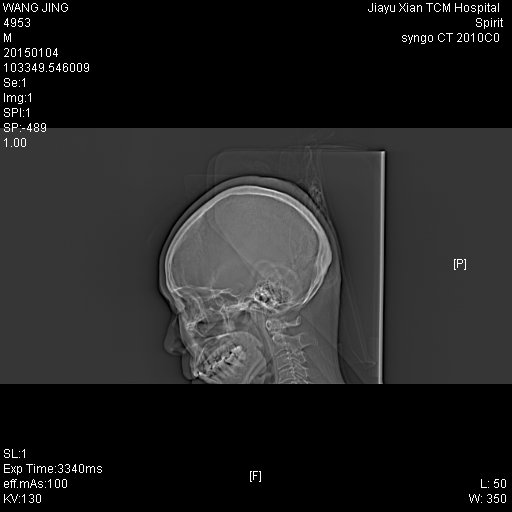

CT49692:患者,女,60岁,因头部碰撞来诊。

右侧人字缝增宽,蛛网膜囊肿

有一部分朱网膜囊肿也可能是外伤后造成的,不过时间应该长了.右侧人字缝增宽.右侧顶部蛛网膜囊肿.顶部脑沟增宽.双侧苍白球点状钙化.

1、平扫示头颅未见明确外伤征象;

2、右侧顶叶近颅骨内板下方低密度灶,扩大的脑沟?先天性蛛网膜囊肿?必要时MR。